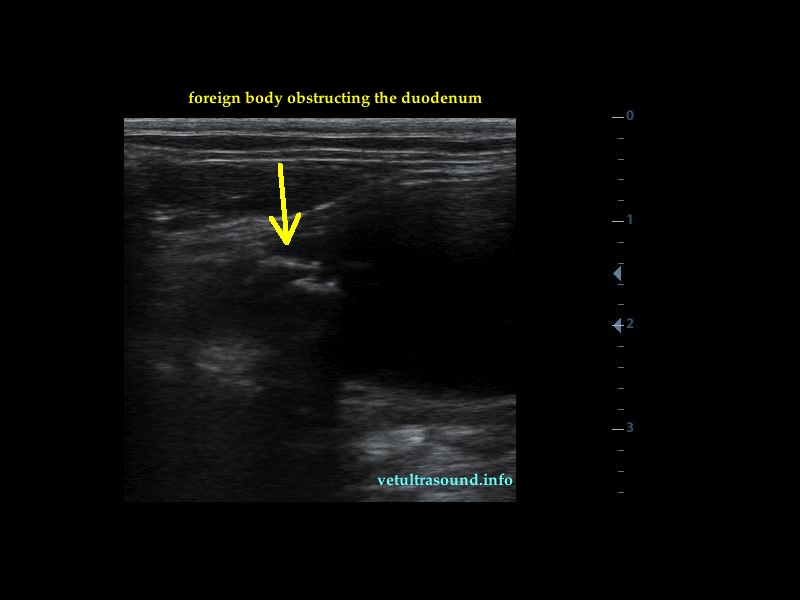

Findings: There was dilation of the stomach and the proximal duodenum. The dilation was caused by a foreign body(pic2). Inside the stomach there were also other foreign bodies floating around(pic1).

pic2